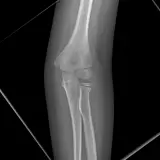

PACS์—์„œ ๊ธฐ๋Œ€ํ•  ์ˆ˜ ์žˆ๋Š” ๋ชจ๋“  ๋„๊ตฌ๋ฅผ ๊ฐ–์ถ˜ ์™„์ „ํ•œ ์ธํ„ฐ๋ž™ํ‹ฐ๋ธŒ ์ฆ๋ก€ — ์Šคํฌ๋กค, ์œˆ๋„์šฐ ์กฐ์ ˆ, ํ™•๋Œ€/์ถ•์†Œ, ํŒจ๋‹, ๊ณ„์ธก, ROI, ์ „์ฒด ํ™”๋ฉด ๋ชจ๋“œ๊นŒ์ง€ ์ง€์›ํ•ฉ๋‹ˆ๋‹ค.

์ฃผ์š” ์†Œ๊ฒฌ์„ ์ฆ๋ก€์— ์ง์ ‘ ํ‘œ์‹œํ•˜๋Š” ํ’๋ถ€ํ•œ ์ฃผ์„์ด ํฌํ•จ๋˜์–ด ์žˆ์Šต๋‹ˆ๋‹ค. ์ฆ๋ก€ ์„ค๋ช…์˜ ์—ฐ๊ฒฐ๋œ ์†Œ๊ฒฌ์„ ํด๋ฆญํ•˜๋ฉด ์Šค์บ” ๋‚ด ์ •ํ™•ํ•œ ์œ„์น˜๋กœ ๋ฐ”๋กœ ์ด๋™ํ•ฉ๋‹ˆ๋‹ค.